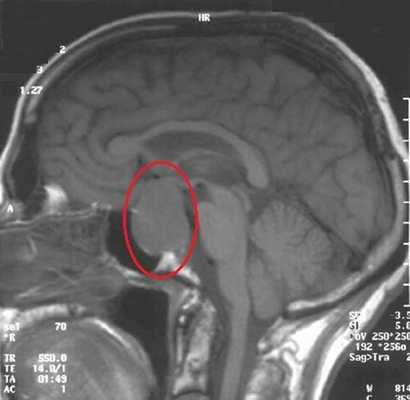

МРТ гипофиза. На МР-томограмме определяется гигантское образование неоднородной структуры (обведено) — макроаденома гипофиза.

Чаще всего исследование проводится для диагностирования аденомы гипофиза и определения ее величины: микроаденомы (до 10 мм), макроаденомы (10—30 мм) и гигантской аденомы (более 30 мм). Также с его помощью обнаруживаются неоднородности структуры, асимметрия границ, изменения положения воронки гипофиза и ее структуры, а также деформации окружающих костных тканей.

Наиболее часто на томограммах обнаруживают аденому гипофиза - доброкачественное новообразование, исходящее из передней доли. Опухоли могут произрастать из любого отдела питуитарной железы, что вызывает многообразие клинических проявлений. Аденома гипофиза локализуется в области турецкого седла, при значительном росте возможно распространение на костные пазухи, желудочки головного мозга, базальную поверхность больших полушарий. Вышеописанные структуры врач может рассматривать в виде многоплоскостных объемных изображений, состоящих из множества срезов, что позволяет уточнить:

- размеры и границы опухоли;

- ее взаимосвязь с окружающими структурами - супраселлярной и мозговой цистернами, перекрестом зрительных нервов, пазухой основной кости, спинкой и бугорком седла, кавернозными синусами и пр.;

- предположительный характер (доброкачественный или злокачественный, первичный или метастатический, окончательная верификация доступна после морфологического исследования). Анализируют постконтрастные снимки, интенсивность накопления красителя (аденомы в подавляющем большинстве задерживают препарат медленнее, чем ткани гипофиза, для злокачественных опухолей характерен усиленный ангиогенез). Дифференциацию проводят с краниофарингиомой, кистой кармана Ратке и арахноидальной жидкостной полостью, имеющих схожие признаки на МР-сканах.

Специалист делает вывод о наличии новообразования гипофиза при обнаружении деформации дна одноименной ямки, асимметрии самой железы, неоднородности ее структуры, смещении воронки от срединной линии.